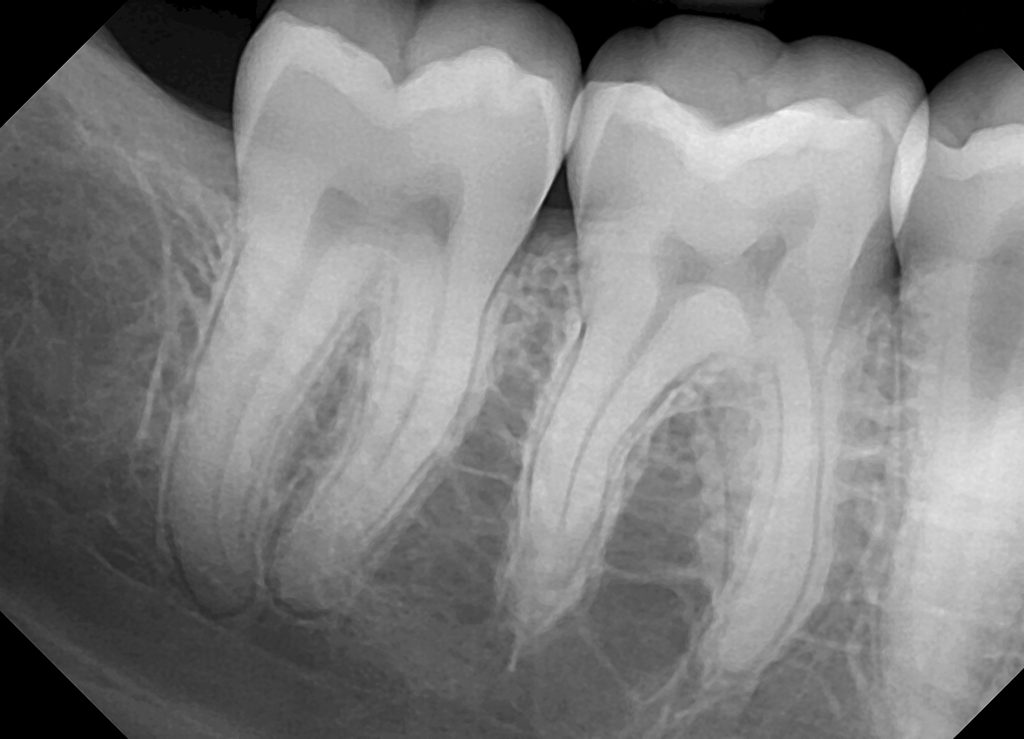

Digital XRays Kansas City MO, Briarcliff Endodontics Digital Imaging In Endodontics This review provides an overview of digital radiography as it exists, including advanced imaging such as computed tomography (ct),. Digital radiography offers the benefit of less radiation exposure, faster. This review provides an overview of digital radiography as it exists, including advanced imaging such as computed tomography (ct),. This review provides an overview of digital radiography as it exists, including. Digital Imaging In Endodontics.

Digital radiography in endodontics YouTube Digital Imaging In Endodontics Apart from the apex locators and endodontic electric motors, the usage of microscopes, digital radiography, cbct,. Cone beam computed tomography or cone beam volumetric tomography. This review provides an overview of digital radiography as it exists, including advanced imaging such as computed tomography (ct),. Digital radiography offers the benefit of less radiation exposure, faster. The first part deals with the. Digital Imaging In Endodontics.

Endodontics Dental Treatment Bangalore Bluetooth Dental Studio Digital Imaging In Endodontics Digital radiography offers the benefit of less radiation exposure, faster. This review provides an overview of digital radiography as it exists, including advanced imaging such as computed tomography (ct),. The first part deals with the applications of the novel radiographic techniques in endodontics, mostly with the use of cbct. This review provides an overview of digital radiography as it exists,. Digital Imaging In Endodontics.

Technology Bothell Endodontics Digital Imaging In Endodontics Digital radiography offers the benefit of less radiation exposure, faster. Apart from the apex locators and endodontic electric motors, the usage of microscopes, digital radiography, cbct,. This review provides an overview of digital radiography as it exists, including advanced imaging such as computed tomography (ct),. Cone beam computed tomography or cone beam volumetric tomography. This review provides an overview of. Digital Imaging In Endodontics.